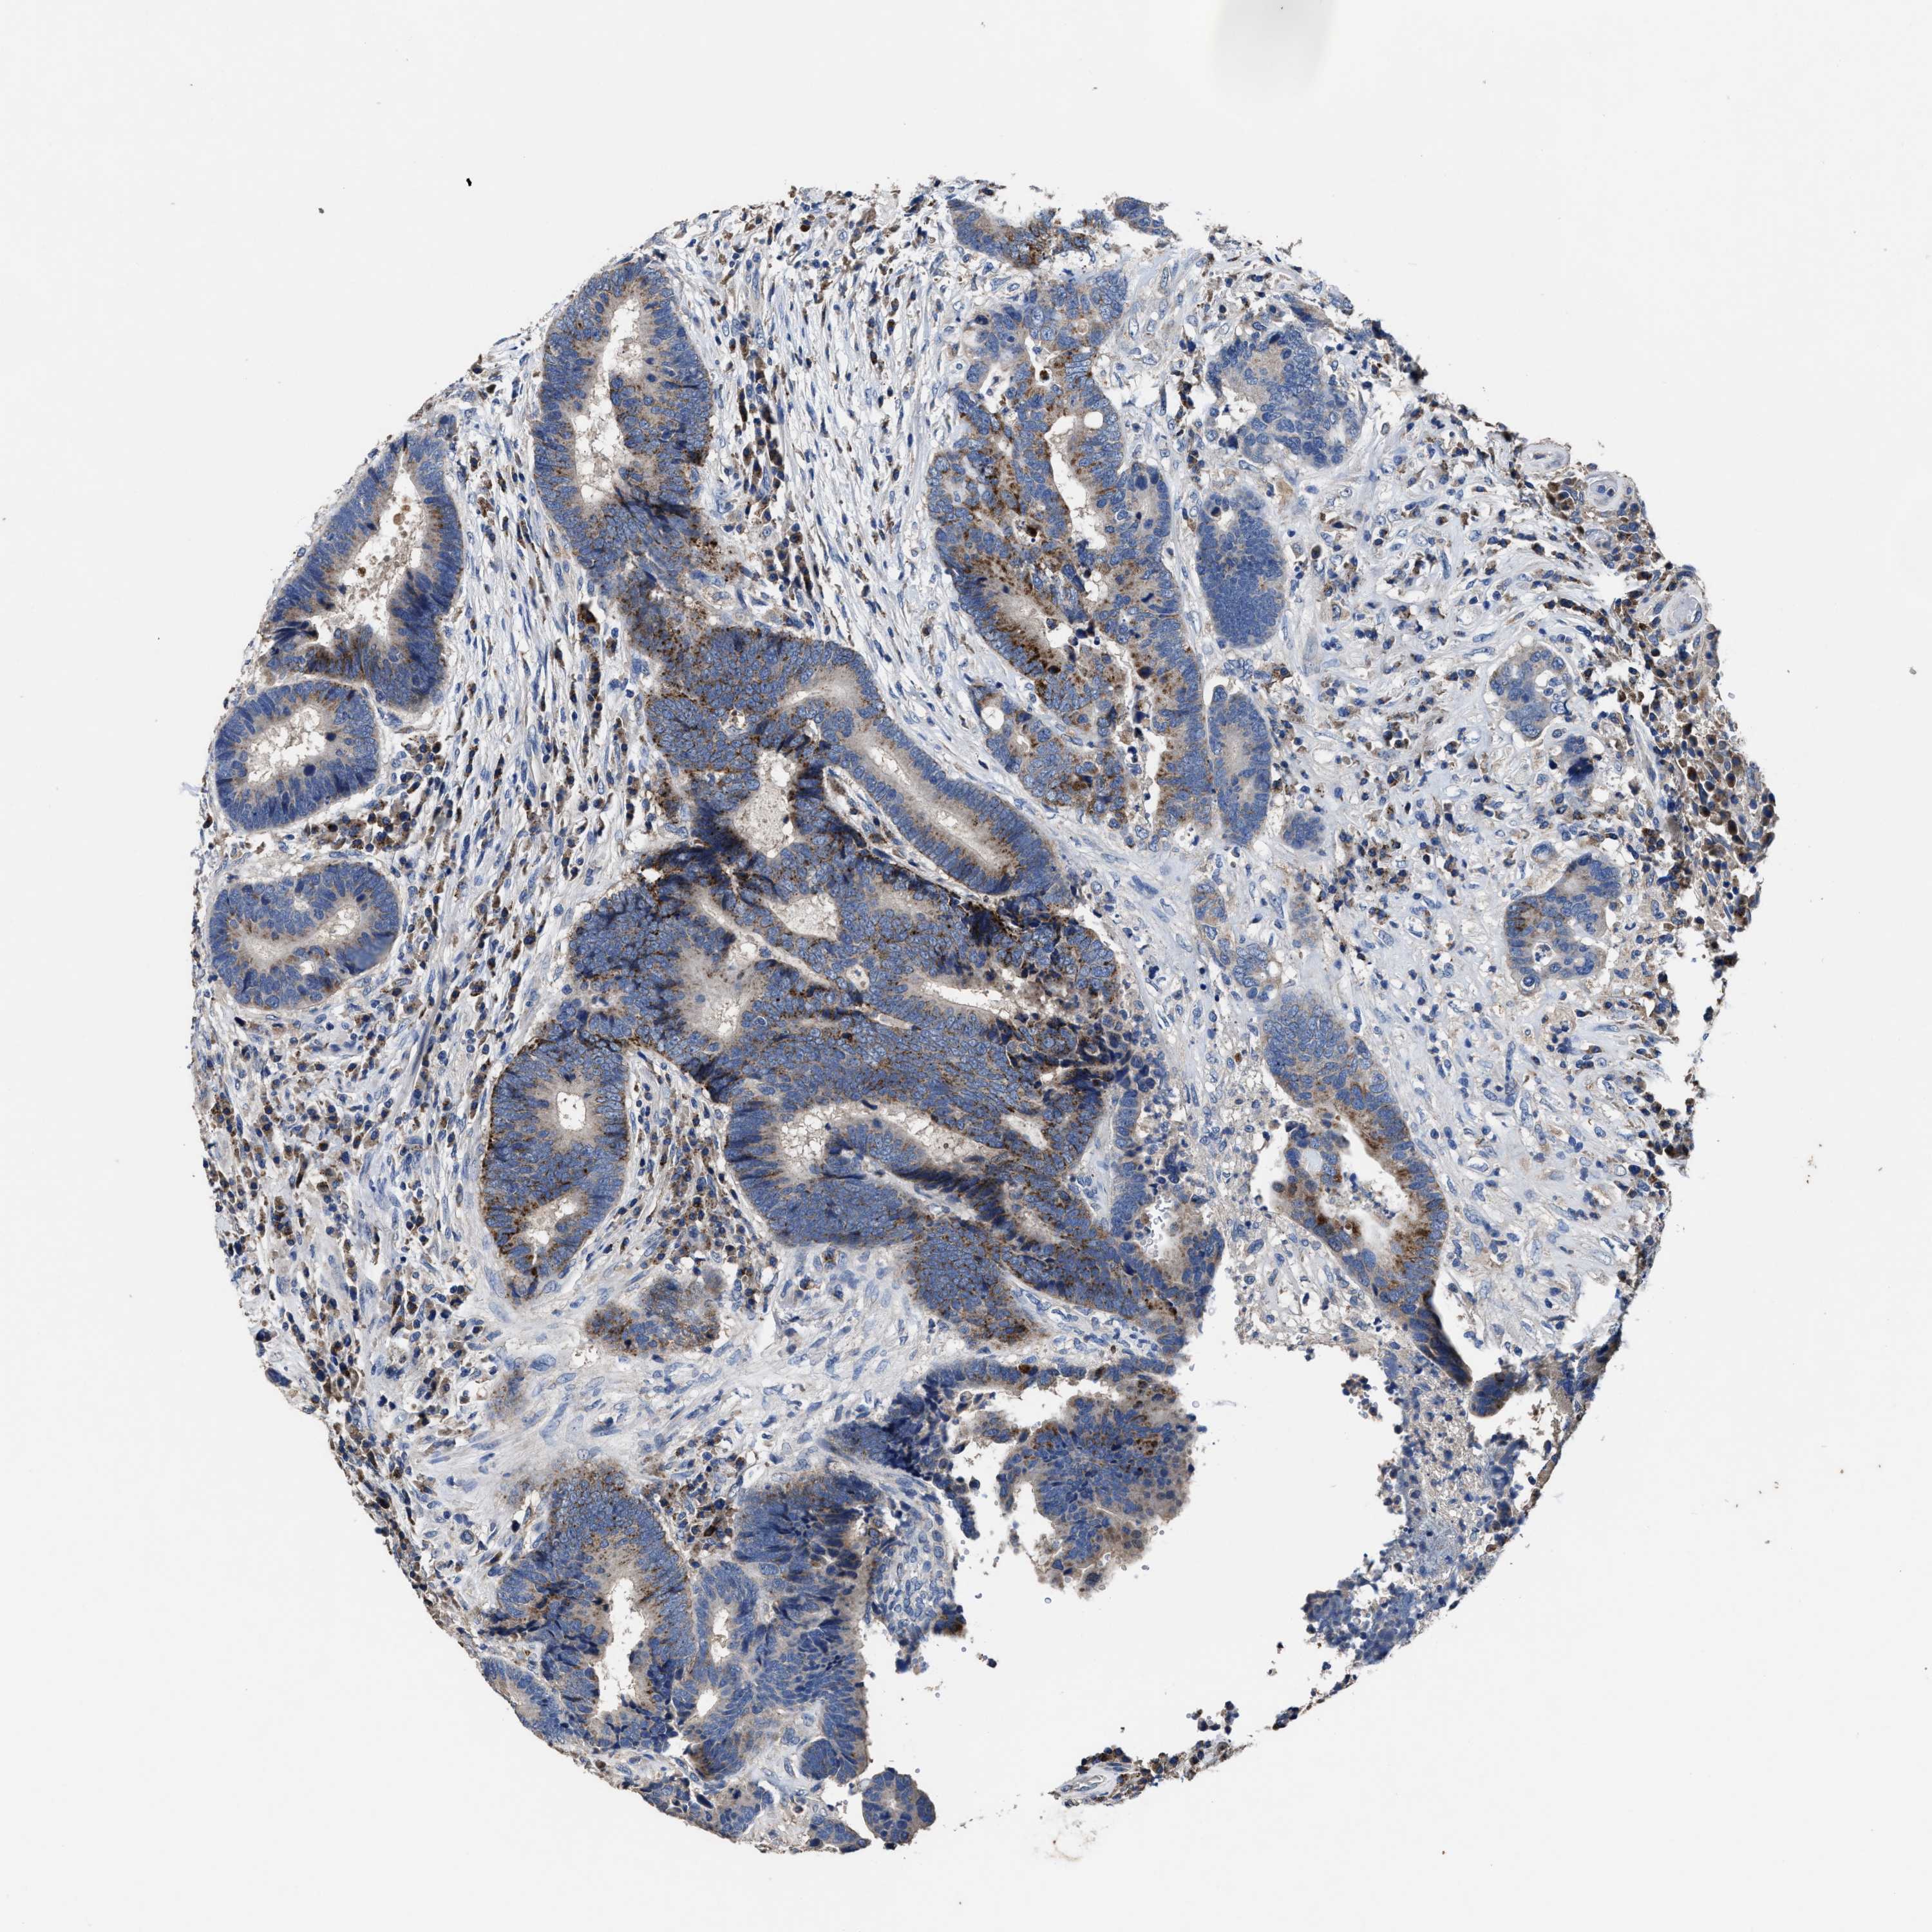

CANCER COLORECTAL CANCER Show tissue menu

ANTIBODIES

AND

VALIDATION